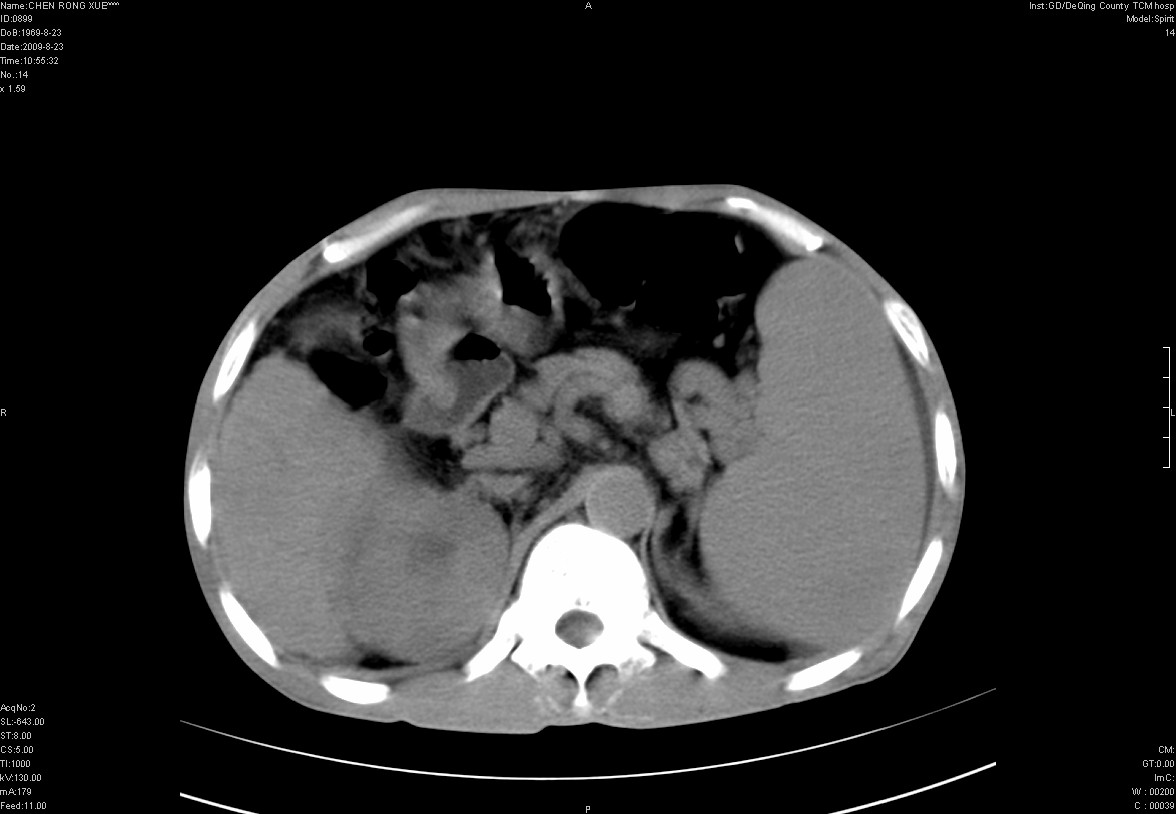

以下是引用zxl51642在2009-8-23 12:56:00的发言:[br]1、肝硬化、脾大;2、慢性胆囊炎;3、右肾占位并右侧腰大肌受侵,考虑恶性可能性大,建议增强扫描进一步检查。

以下是引用qiuleiyu在2009-8-23 15:17:00的发言:[br]1、慢性肝病,肝硬化,脾大,门脉高压。胆囊小结石。[br]2、右肾明显肿大,伴片状低密度灶,累及右侧腰大肌,肿瘤及炎症性病变皆有可能大,建议增强。

以下是引用zjzjr在2009-8-23 17:42:00的发言:[br]1、慢性肝病,肝硬化,脾大,门脉高压。胆囊小结石。[br]右肾脓肿波及肾周,建议增强